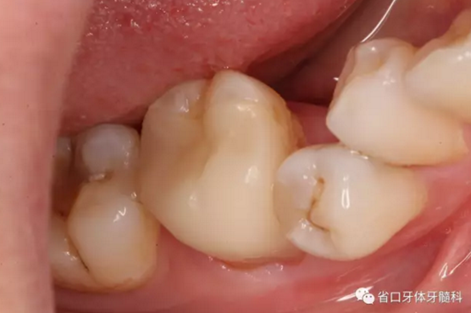

圖4 牙體預(yù)備后頰側(cè)觀